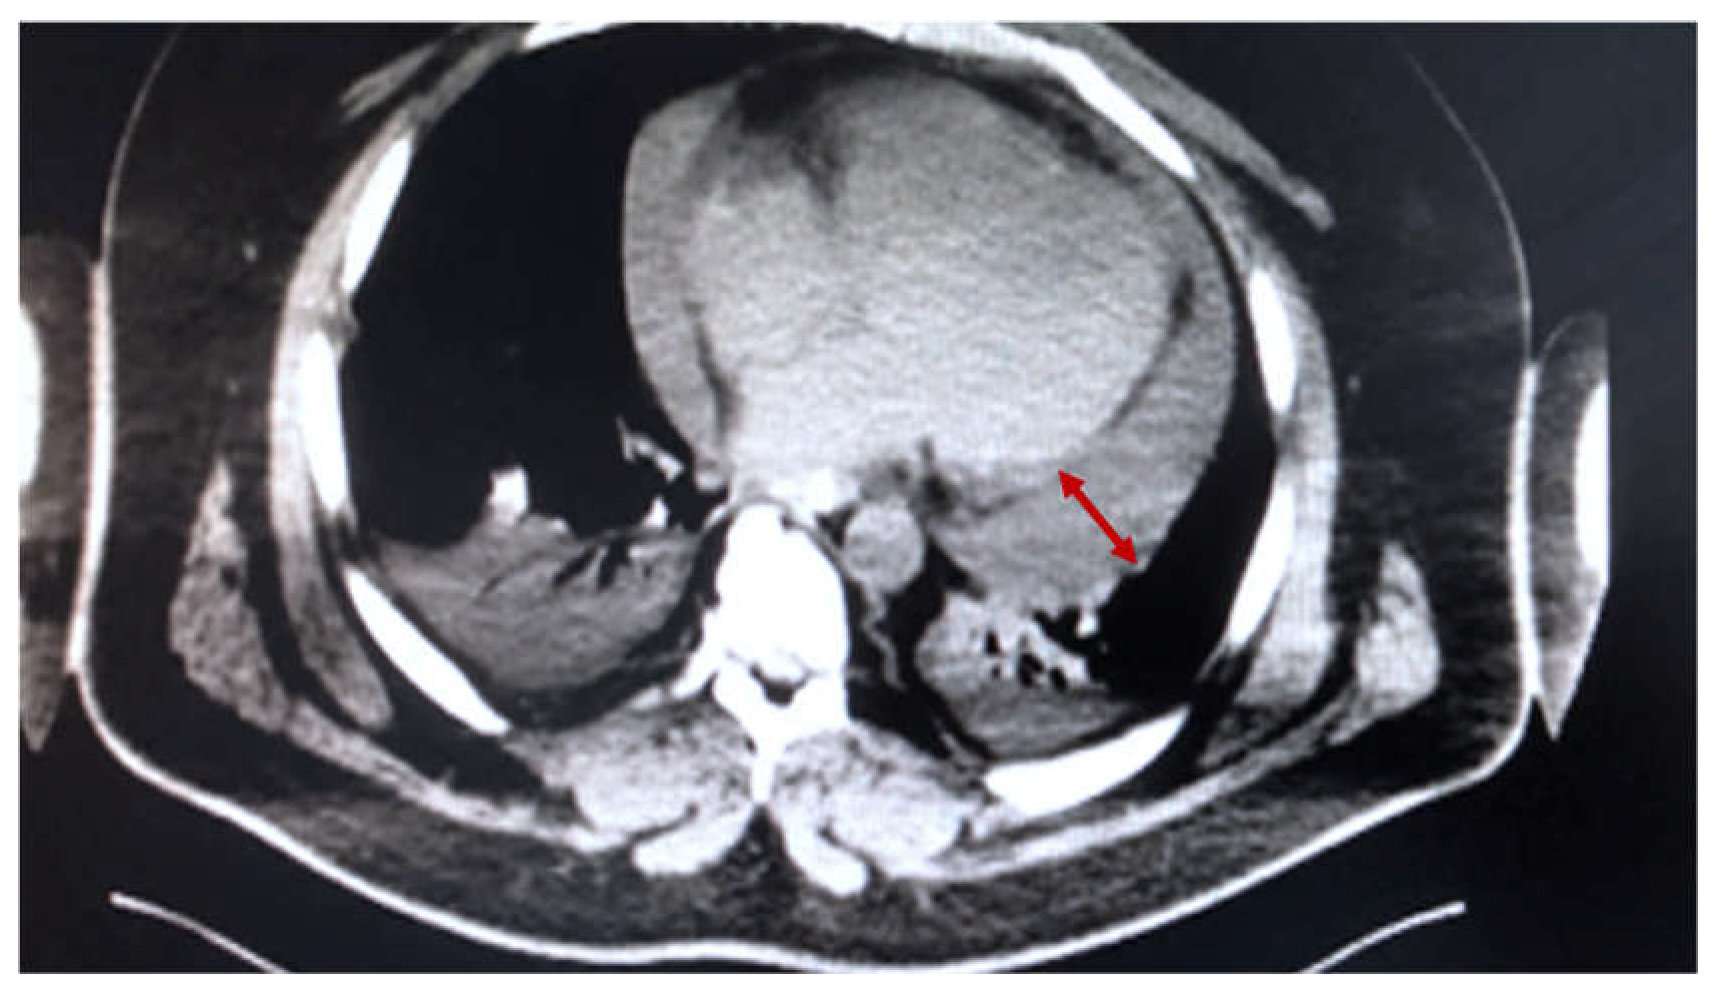

2.2. Case 2